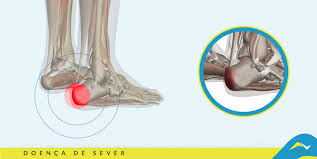

Esporão de Calcâneo

É uma formação óssea que ocorre no calcâneo (osso da base do calcanhar). Ao longo dos anos pequenos fragmentos ósseos resultado do desgaste do corpo, aglomeram-se e formam uma espícula, também conhecida por "esporão". que causam fortes dores nos pés.

A dor só ocorre quando é feito o apoio de carga ou pressão no local. Está relacionado também com obesidade e com o aumento súbito de atividades diárias.